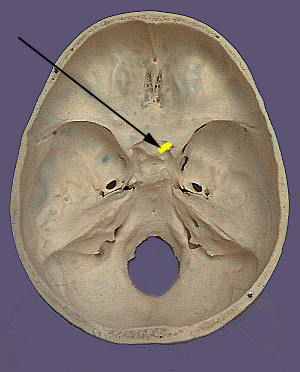

Optic Nerve Cranium CN II

CN II. Optic Nerve

The optic nerve originates from the bipolar cells of the retina which are connected to the specialized receptors in the retina (rod and cone cells).  Light strikes the rod and cone cells and electrical impulses are transduced and transmitted to the bipolar cells. The bipolar cells in turn transmit electrical activity to the central nervous system through the optic nerve. The optic nerve exits the back of the eye in the orbit and enters the optic canal and exits into the cranium. It enters the central nervous system at the optic chiasm (crossing) where the nerve fibers become the optic tract just prior to entering the brain.